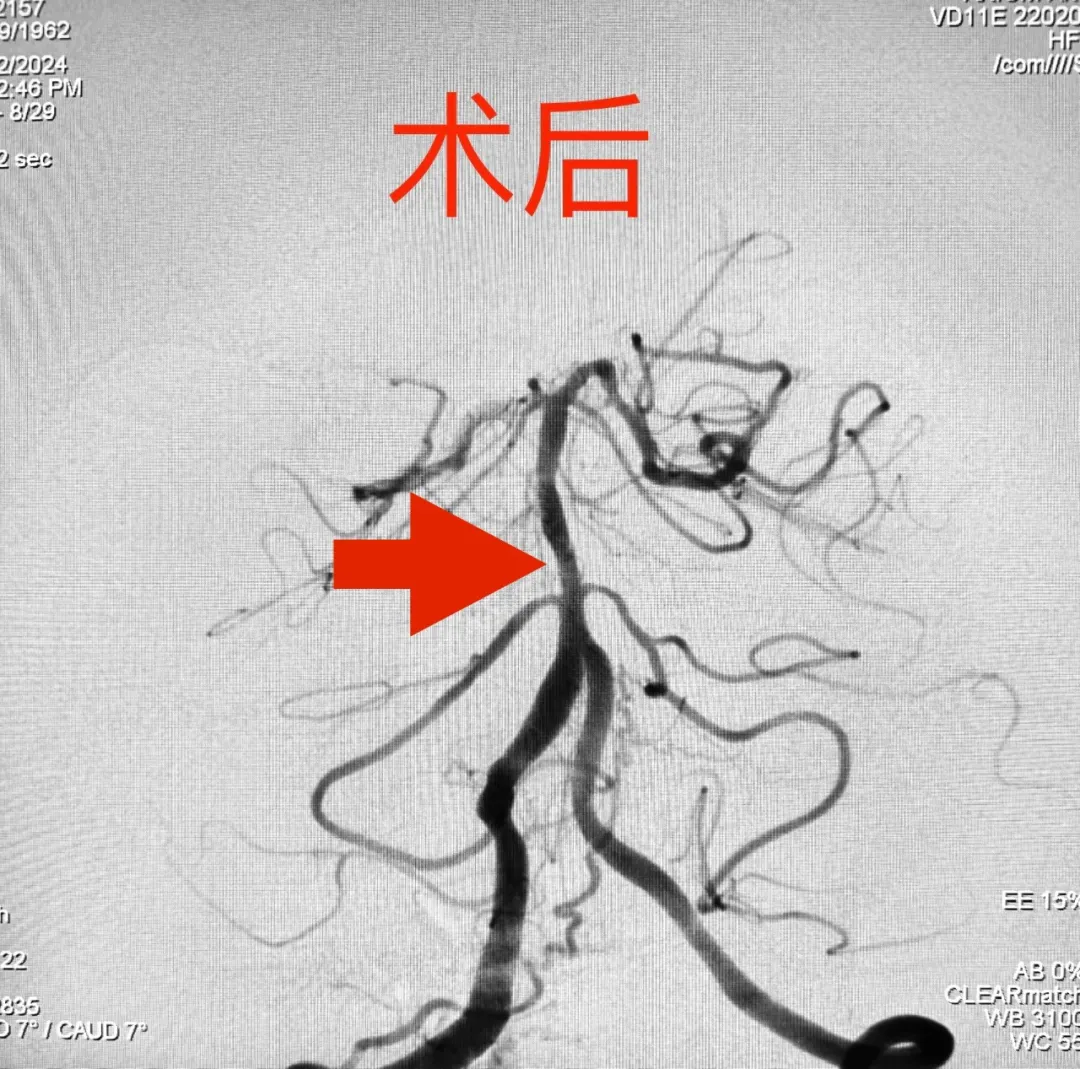

为保证治疗效果,同时减轻患者经济负担,减少手术费用,尽可能地做到不放支架,实现“有介入、无植入”的理想境界,在麻醉科、手术室、介入导管室的共同协作下,手术如所有人期待的那样非常顺利,通过精准定位锁定病变血管狭窄处,实施单纯球囊扩张,扩张后造影显示,狭窄段血管管径恢复满意,血流得到明显改善,手术后麻醉苏醒快;术后,患者头晕症状明显缓解,行走自如,该患者血管狭窄的改善也大大降低了脑梗死再次复发的风险。

由于恢复很快,患者住院不到7天就要出院了,临别时,他紧紧握着高主任的手迟迟不愿松开,对神经内科医护团队在住院期间的给予的精心治疗与暖心照顾表示感激,对高小平主任团队的精湛技术坚起了大拇指,嘴里不停的念着:自己太幸运啦,能够遇到高主任,一次微创手术就解决了他的大问题,而且花费不多,并表示一定听从医嘱,坚持规律服药,6个月后准时来医院复查。